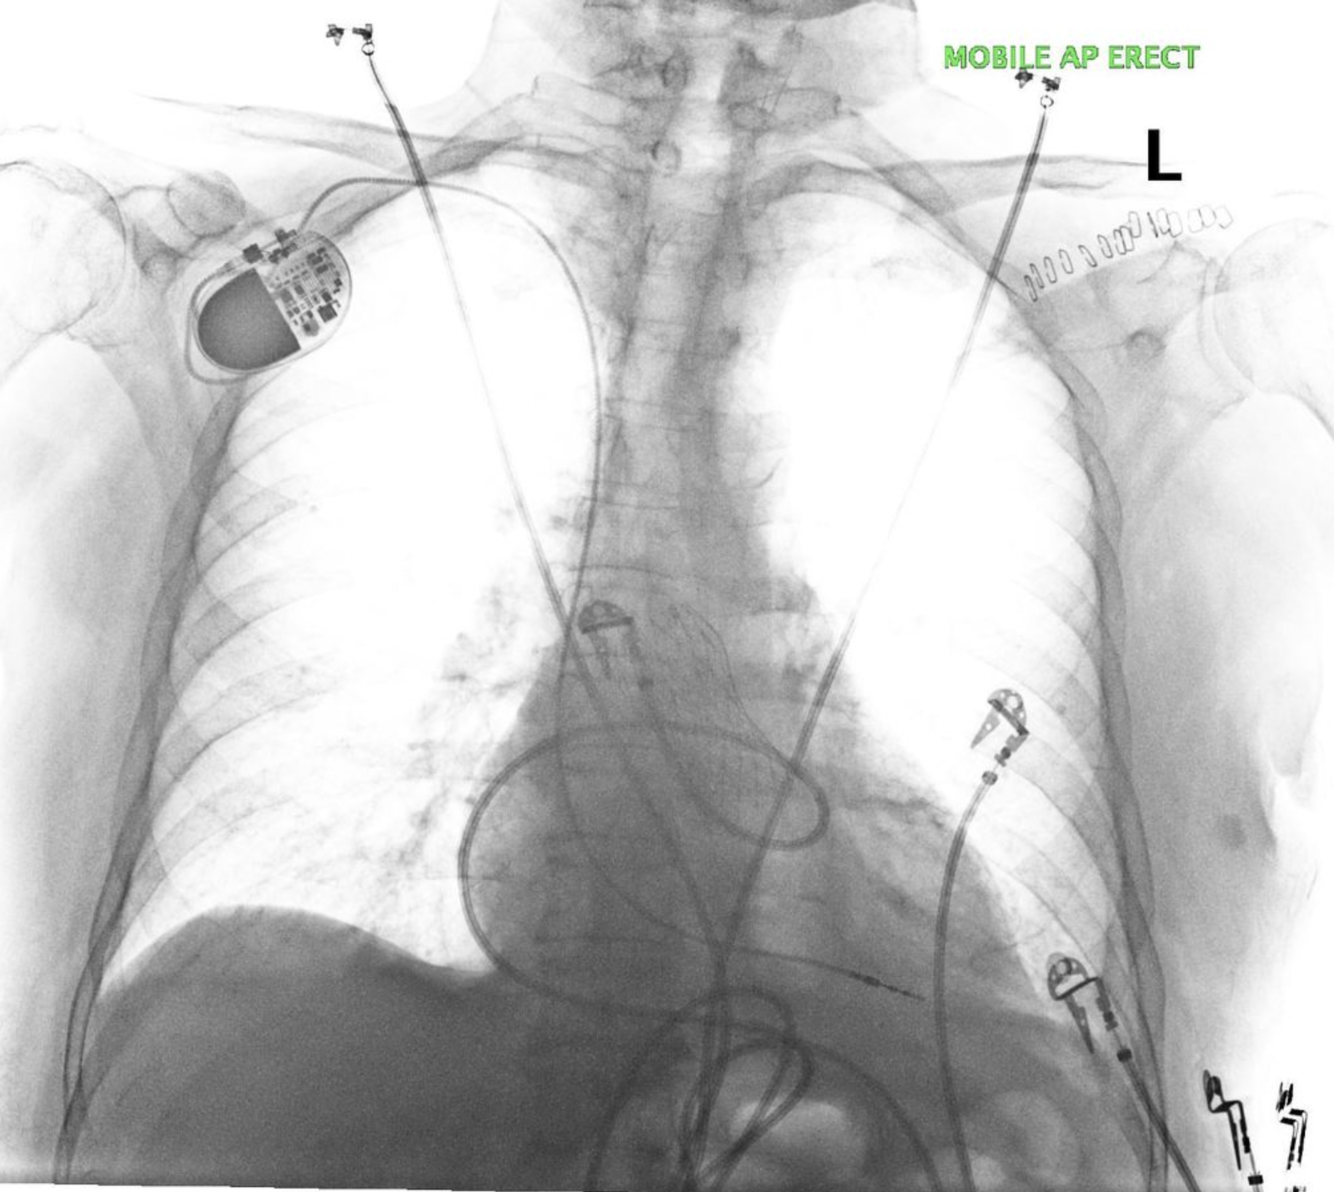

-Dual chamber ICD

-LVAD implanted